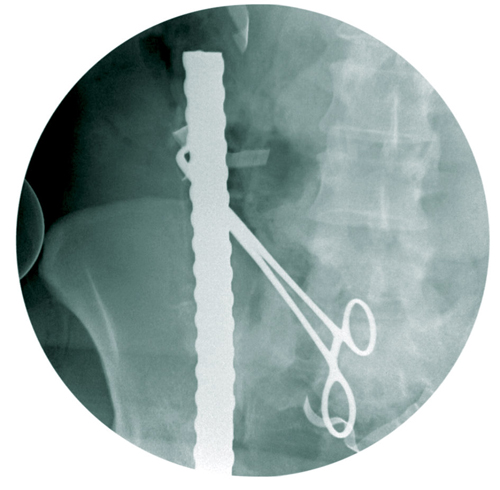

وبينت السبيعي أن السيخ الأول اخترق الجزء الأيمن من منطقة الفخذ بمحاذاة الشريان والوريد الفخذي الفرعي والأساسي مع منطقة البطن بمحاذاة الشرايين الحرقفية الكبرى وصولاً إلى شرايين الكلية اليمنى واستقر بمحاذاة الاثنى عشر نتج عنه إصابة طفيفة في الاثنى عشر، مشيرةً إلى أن صور الأشعة أوضحت بأن السيخ الثاني اخترق منطقة البطن السفلى تحت السرة مما أدى إلى إصابة الأمعاء الدقيقة في أربع مناطق واستقر في الجزء العلوي من المعدة بعد اختراق الجدار الخلفي والأمامي للمعدة، أما السيخ الثالث تبين أنه اخترق الحوض من الجهة اليسرى مما أدى إلى كسر مضاعف في تلك الجهة من الحوض واستقر بمحاذاة العمود الفقري دون اختراقه ولله الحمد. وأفادت أن مثل هذه الإصابات يستلزم إجراء جراحة لها من خلال فريق جراحي متمكن وبدقة عالية من المهارة لما فيها من خطورة بالغة على حياة المصاب، وحول مراحل العملية أوضحت السبيعي أن السيخ الأول تم استخراجه بعد السيطرة على الشرايين الكبرى، أما السيخان الآخران فقد تمت إزالتهما بعناية شديدة كي لا تؤثرا على الأعضاء المحيطة بالمنطقة المصابة مع ترميم الأعضاء المتأثرة جراء هذه الإصابة.